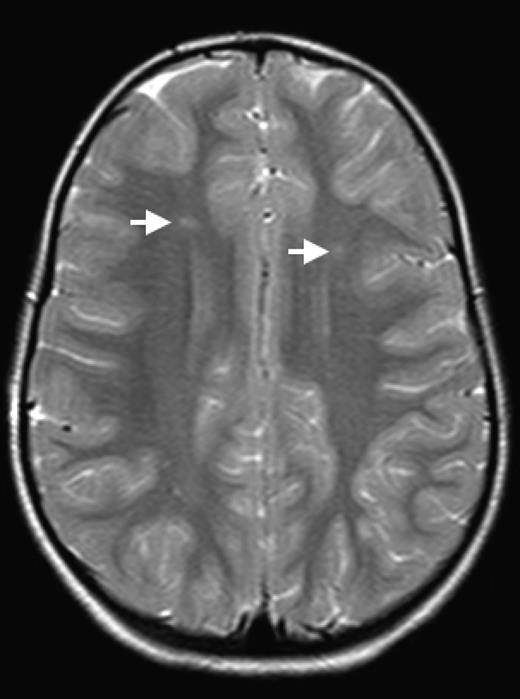

The brain is at constant threat of ischemic injury in sickle cell disease (SCD). The risk of overt stroke for children with SCD is more than 200 times higher than that for the general population, and this burden of overt stroke continues well into adulthood. An even more common form of neurologic injury in SCD is silent cerebral infarction (SCI), which has a prevalence of up to 40%. SCI refers to generally small, permanent brain lesions that are not associated with obvious focal neurologic signs (Figure 1). The term SCI is a misnomer because these strokes, even though they do not produce focal or localizing signs on neurologic examination, are often not “silent.” SCI is a morbid condition associated with neurocognitive impairment, poor academic performance, neurologic soft signs, and increased risk for subsequent overt stroke. Covert cerebral infarction may be a better descriptor, but SCI is the accepted term.

SCI. Two typical SCI lesions (arrows) are shown in the frontal and deep white matter in a T2-weighted magnetic resonance image of the brain in a child with sickle cell anemia.

The definition of SCI has 2 components: (1) an infarct-like lesion on MRI of the brain and (2) a normal neurologic examination or no abnormality on neurologic examination that can be explained by the location of the infarct-like lesion. Specific definitions of the SCI lesion on MRI vary by study, but the Silent Cerebral Infarct Transfusion (SIT) Trial (www.ClinicalTrials.gov identifier #NCT00072761) rigorously defined it to be an MRI signal abnormality (increased signal) of at least 3 mm in 1 dimension that was visible on at least 2 views of T2-fluid-attenuated inversion recovery images of the brain.1 Because SCI is clinically covert, it must be identified by screening MRI of the brain. SCI is therefore almost always identified incidentally as a remote event well after its onset, which makes the study of its causes and frequency quite challenging. The goal of this chapter is to highlight several of the recent advances in our understanding of the frequency, risk factors, correlates, causes, and management of SCI.